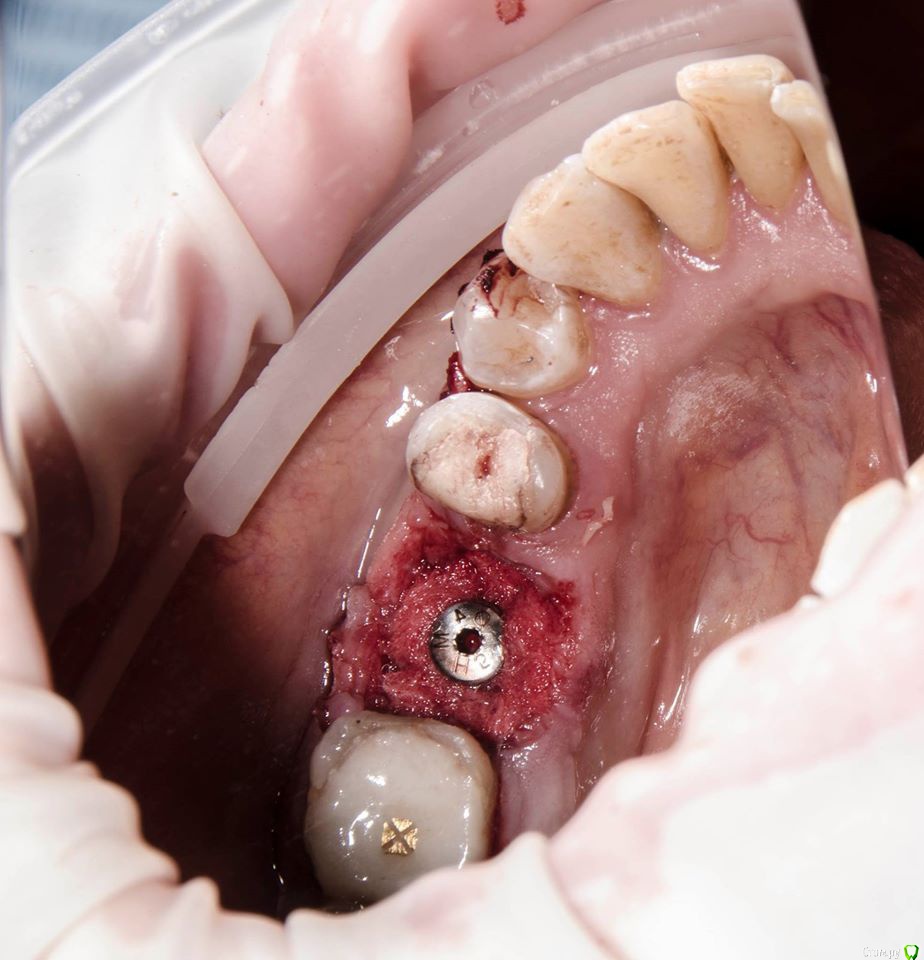

kamranchick Опубликовано 29 марта, 2016 Поделиться Опубликовано 29 марта, 2016 Не надо в рану альвостаз пихать, по опыту он только мешает заживлениюОлег, как вы думаете, можно ли так поступать? тут мембраны нет, только алвостаз Ссылка на комментарий